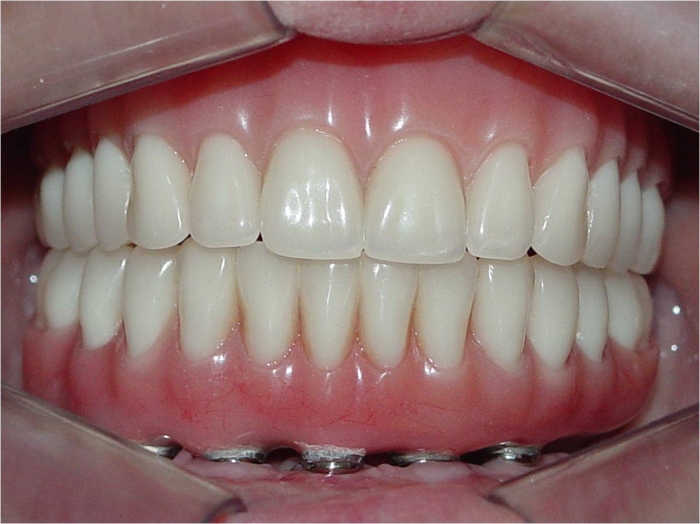

Imagem final

Sorriso final, do caso terminado em setembro de 2013